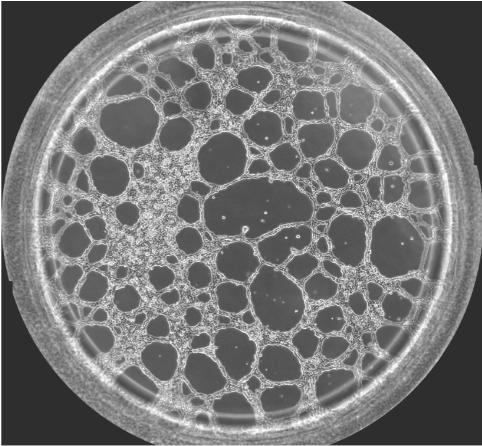

圖一  血管生成鏡檢圖

提前將Matrigel融化,鋪于ibidi血管生成載玻片的下孔中,待膠凝后,將細胞懸液加入血管生成載玻片上孔中,成管后使用顯微鏡觀察。